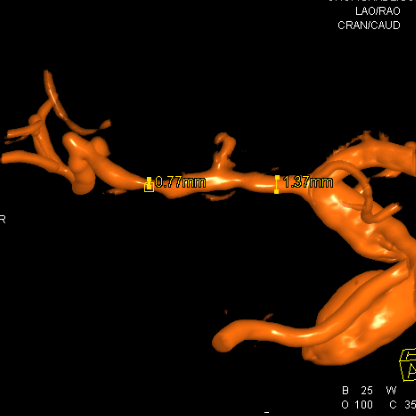

5、粗大豆纹动脉的远端和近端都有一个狭长的血管变细

血管直径测量

血管形态

放大后仔细观看,近端有局限性血管变细,并见双腔征

另外时相远端也隐约局限性变细

测量